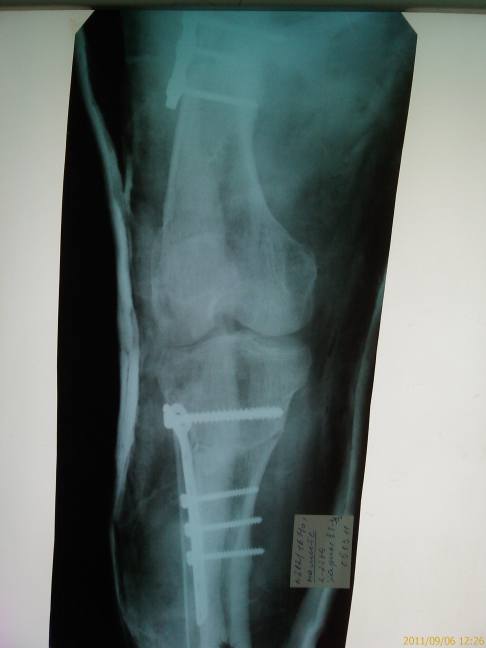

Имя     : правя голень.jpg

Тип     : image/jpeg

Размер  : 24853 байтов

Описание: отсутствует

Url     : http://weborto.net:8080/pipermail/ortho/attachments/20110910/89848992/attachment-0005.jpg

Удаление сломанного стержня правой бедренной кости, ресинтез бедра пластиной

с коррегирующей остеотомией  и костной аутопластикой, коррегирующая

остеотомия правой большеберцовой  кости остеосинтез пластиной.  Продолжил

лечение амбулаторно. Иммобилизация 12 недель. .

Деформирующий остеартроз 3 степени коленных суставов. Состояние после

корригирующих операций на голенях и бедрах по поводу варусной деформация